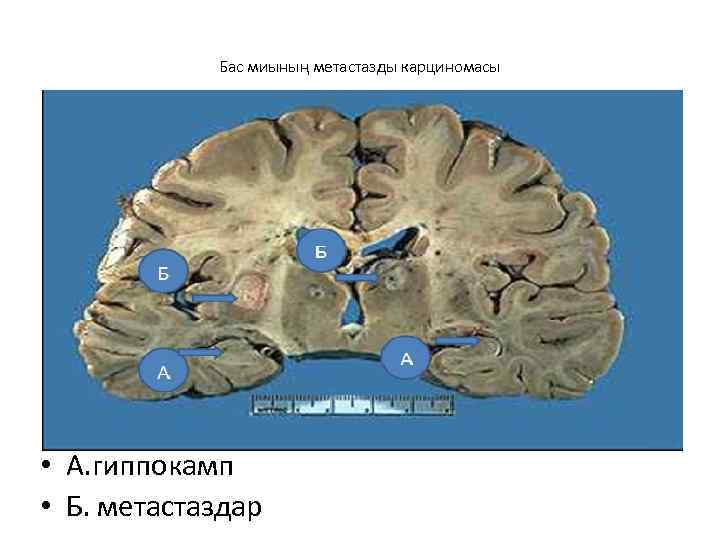

Бас миының метастазды карциномасы • А. гиппокамп • Б. метастаздар